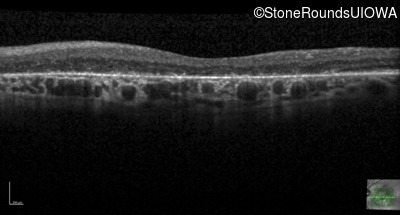

Age at visit: 58 years

OD OS

This 58 year old woman first noticed a gap in the vision of her left eye at age 46.

Age at visit: 58 years (Visit 2)